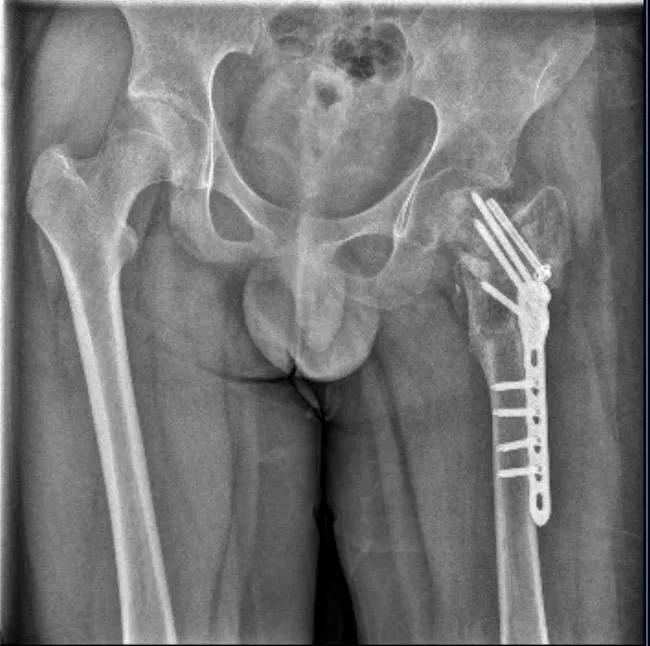

然而此后,四维基地仍继续招生运营。2024年,武女士听一名家长说,基地里的孩子更多了,有孩子“因为逃跑被吊着打”。武女士再次报警。7月,晋江市公安局对小武被故意伤害一案立案侦查。随后,晋江市公安局对小武进行了人体损伤程度鉴定,8月29日出具的《鉴定意见通知书》显示,小武三个部位不同程度损伤,其中,“左髋部重伤二级,胸部轻伤一级,双下肢轻微伤”,同时,其左股骨打了钢针、钢板。